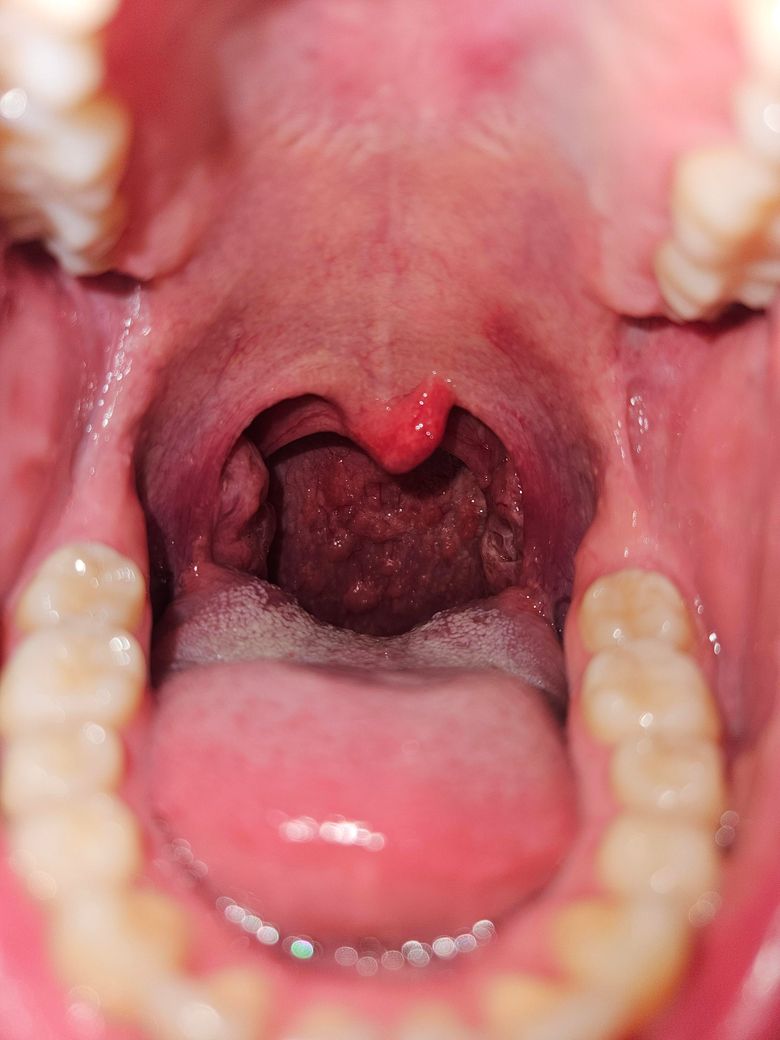

특히 혀는 하얀게 원래도 많았지만 평소보다 많아졌고 빨간 반점 같은 것과 식도 근처에 종기 같은게 보입니다... 사진에는 안보이지만 입 천장에는 만져도 안아픈 혹이 한 두개 정도 만져지고 혀 뒷쪽은 더 큰 종기 같은게 육안으로 더 보입니다.

• 2번 째 사진

말씀하신 증상들, 목의 이물감, 혀의 종기, 입안의 붉은 반점, 체감되는 몸살 기운 등은 감기나 인후염 같은 일반적인 감염일 가능성도 있지만, 최근 구강 성교와 키스 이력으로 인해 구강 성병의 가능성도 배제할 수 없습니다. 특히 헤르페스, 매독, 임질, 클라미디아 같은 질환은 구강 내에서도 감염이 일어날 수 있으며, 일부는 통증 없는 궤양이나 반점, 종기 형태로 나타나기도 하죠